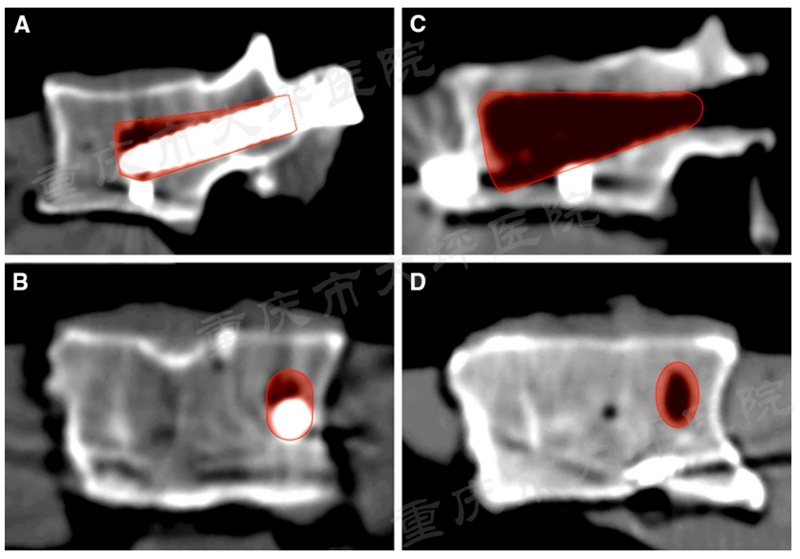

腰椎滑脱症是一种上位椎体相对于下位椎体向前滑移,以腰腿痛、间歇性跛行为主要症状的常见退变性脊柱疾病,成年人发病率约为6%。对于保守治疗无效的患者,采用后路椎弓根螺钉内固定技术复位滑移椎体、恢复腰椎序列、坚强固定达到骨融合是主要的治疗方式。然而,老年骨质疏松人群由于骨质疏松极大的降低了椎弓根螺钉的稳定性,极易发生内固定失败(图1)。

图1 腰椎滑脱内固定失败病例

课题组前期的回顾性病例对照研究证实,单侧使用PMMA螺钉(2颗)与双侧使用PMMA螺钉(4颗)具有相近的临床疗效,成功将PMMA螺钉使用的推荐数量从4颗减少为2颗。进一步观察发现,普通椎弓根螺钉失效模式为“雨刮效应”(图2)。

图2 CT扫描示意“雨刮效应”

骨水泥增强椎弓根螺钉后,由于骨-钉界面的应力分布特征被人为改变,失效模式与普通螺钉相比也发生了变化,将其称为“反雨刮效应”(图3),该现象的生物力学机制尚不清楚。课题组敏锐的发现,在其背后可能蕴含着合理应用PMMA螺钉的关键线索。

图3 “反雨刮效应”示意图